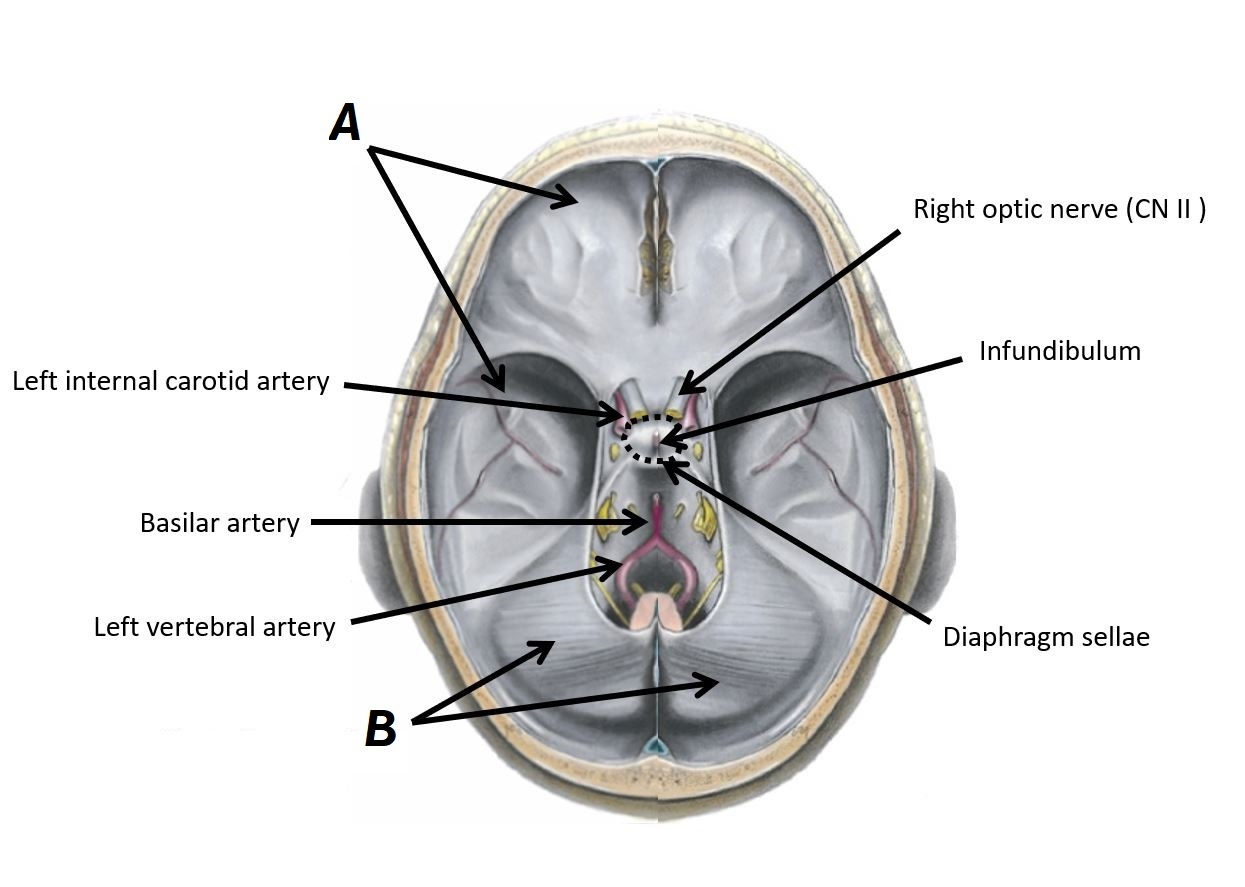

Name structures A and B

A - Dura mater

B - Tentorium cerebelli

Name structure A and region B

A - Infundibulum

B - Diaphragm sellae